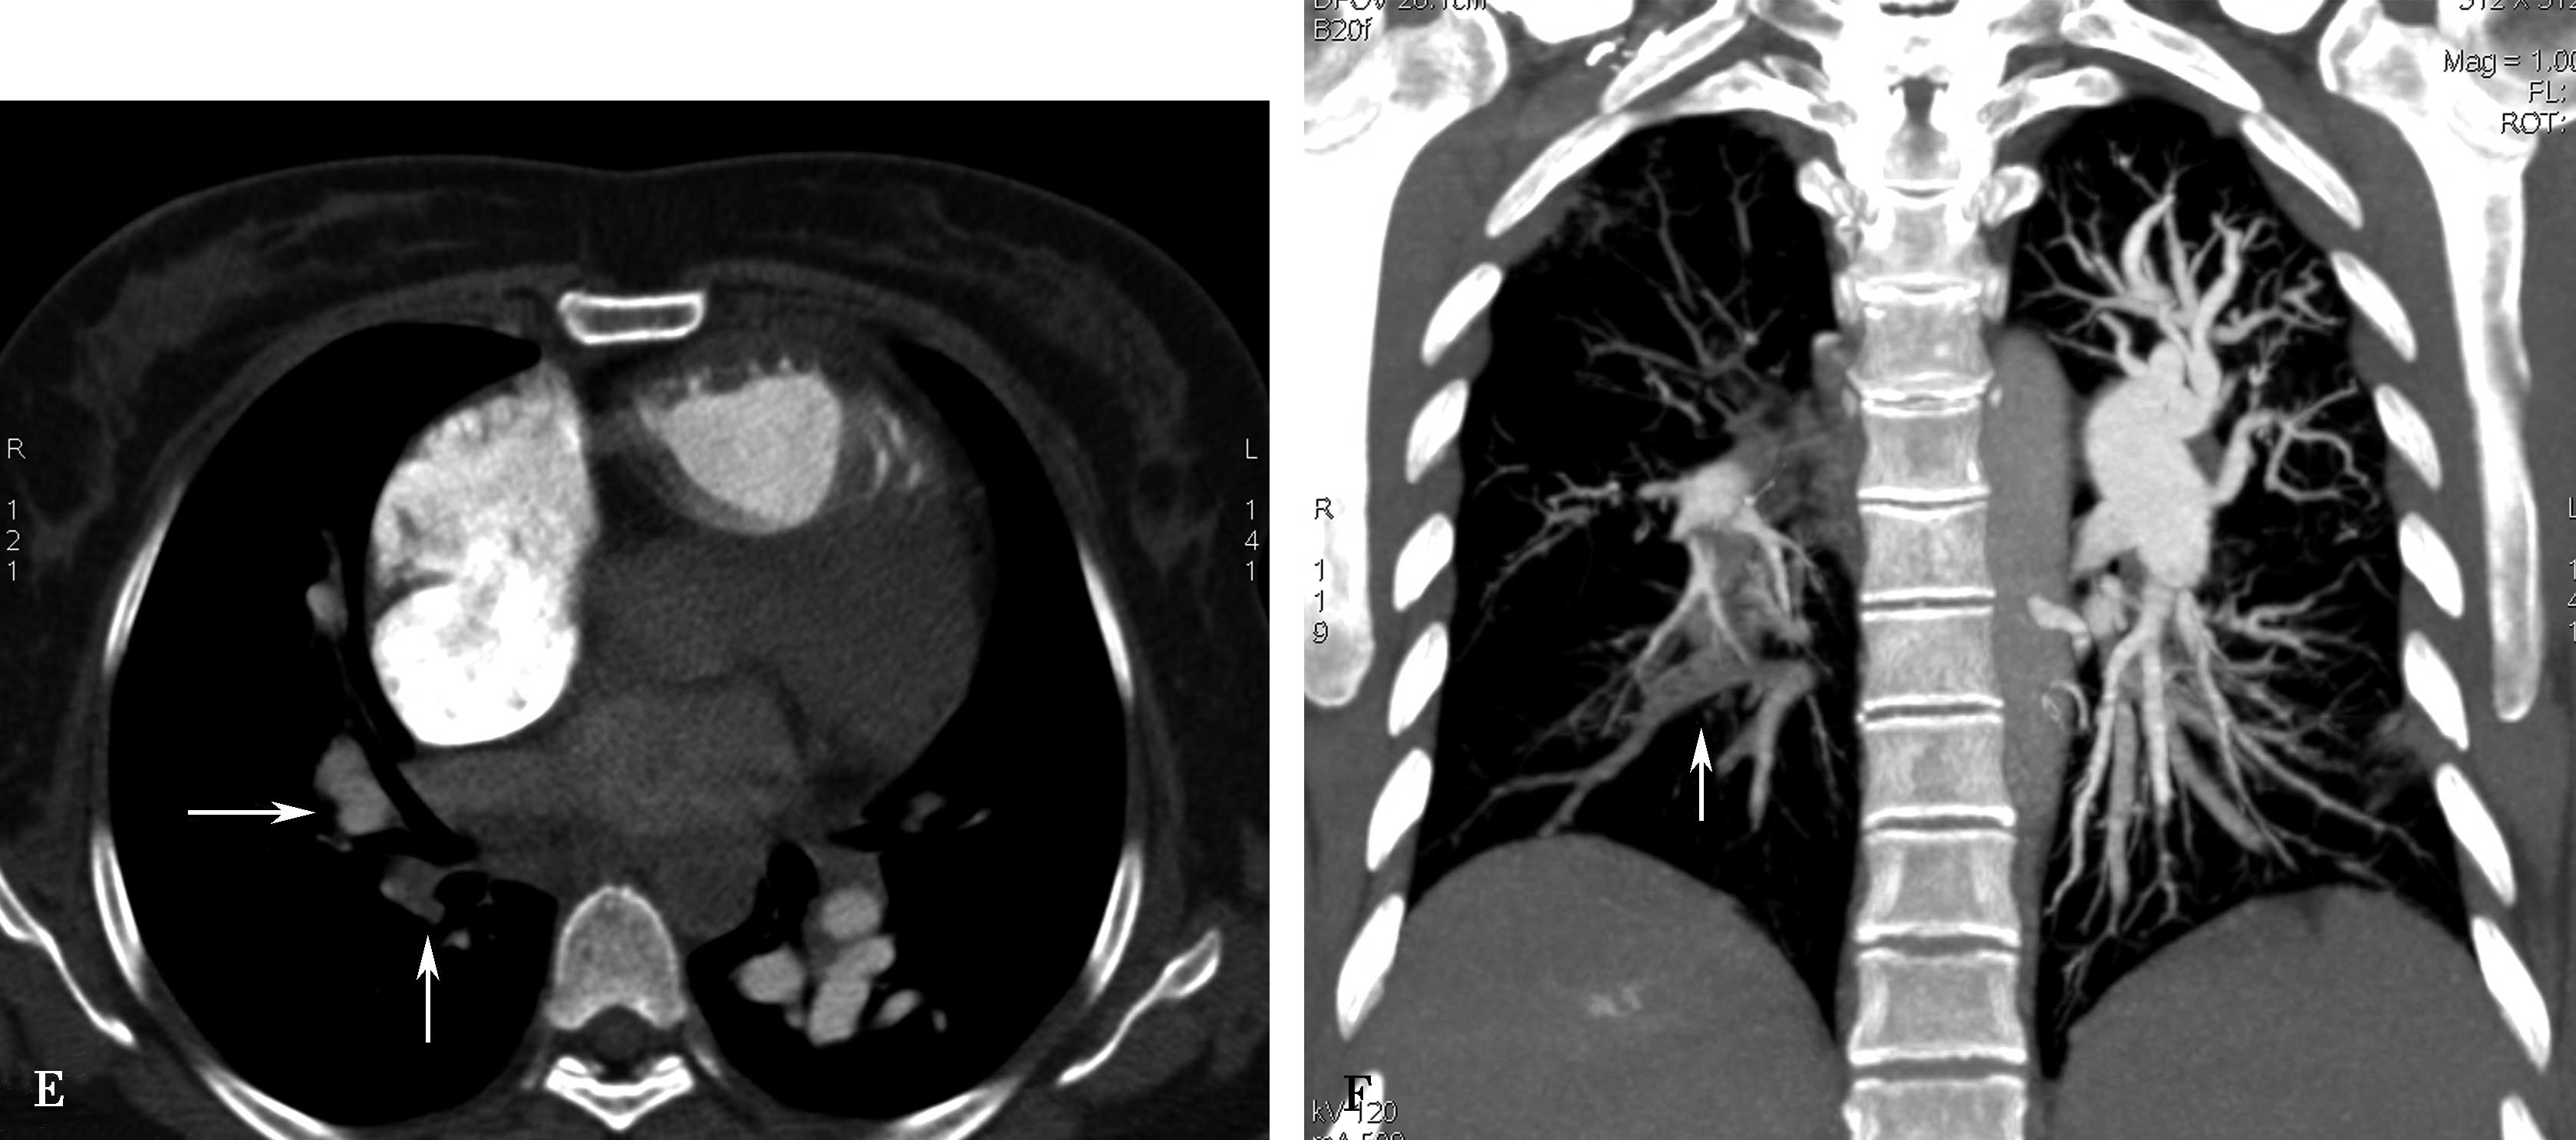

图8-1-5 CTPA两期扫描应用:患者,男,37岁,二尖瓣狭窄,肺循环高压,怀疑肺栓塞。第一期右肺下叶基底段对比剂充盈不充分(ABC↑);第二期充盈充分(DEF↑),排除肺栓塞诊断